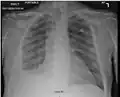

There are three key elements to the diagnosis of silicosis. First, the patient history should reveal exposure to sufficient silica dust to cause this illness. Second, chest imaging (usually chest x-ray) that reveals findings consistent with silicosis. Third, there are no underlying illnesses that are more likely to be causing the abnormalities. Physical examination is usually unremarkable unless there is complicated disease. The examination findings are not specific for silicosis.[19]

For uncomplicated silicosis, chest x-ray will confirm the presence of small (< 10 mm) nodules in the lungs, especially in the upper lung zones. Using the ILO classification system, these are of profusion 1/0 or greater and shape/size "p", "q", or "r". Lung zone involvement and profusion increases with disease progression. In advanced cases of silicosis, large opacity (> 1 cm) occurs from coalescence of small opacities, particularly in the upper lung zones.

With retraction of the lung tissue, there is compensatory emphysema. Enlargement of the hilum is common with chronic and accelerated silicosis. In about 5–10% of cases, the nodes will calcify circumferentially, producing so-called "eggshell" calcification. This finding is not pathognomonic (diagnostic) of silicosis. In some cases, the pulmonary nodules may also become calcified.

Chest X-ray showing uncomplicated silicosis Chest X-ray showing uncomplicated silicosis